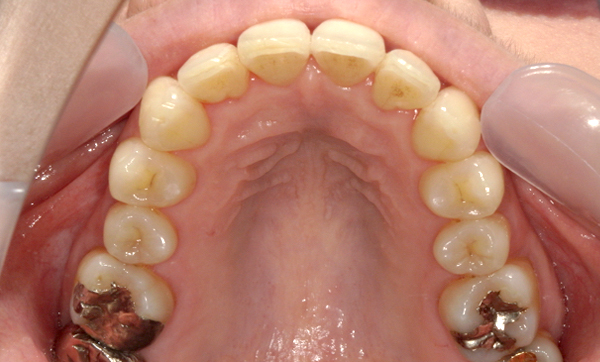

症例_001 上顎だけの部分矯正

治療期間:8ヶ月金額:24万円+税男性すきっ歯上の前歯だけ

| Before | After |